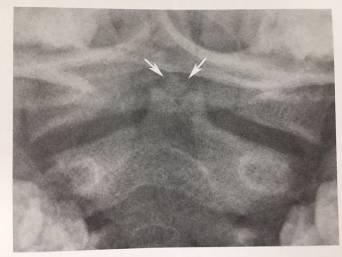

13、寰椎后弓旁正中央裂

寰椎后弓旁中央裂为正常变异,易误为骨折。